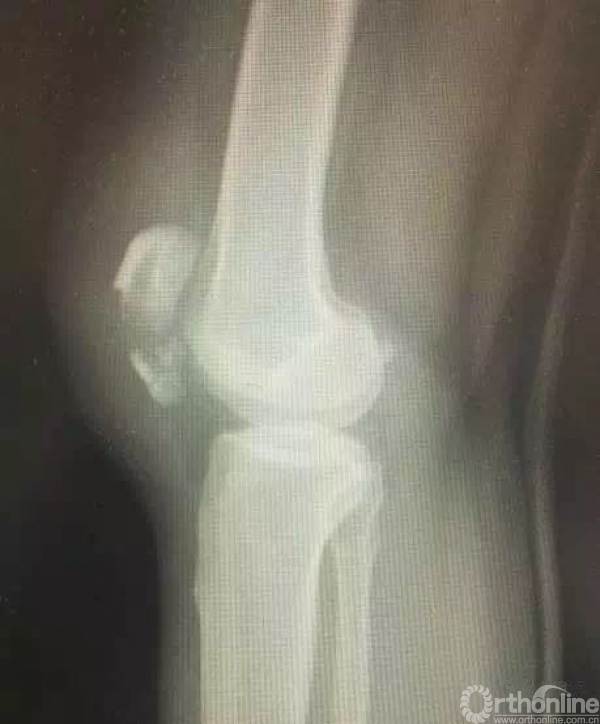

术前X线,下级粉碎,中下段上下分层。